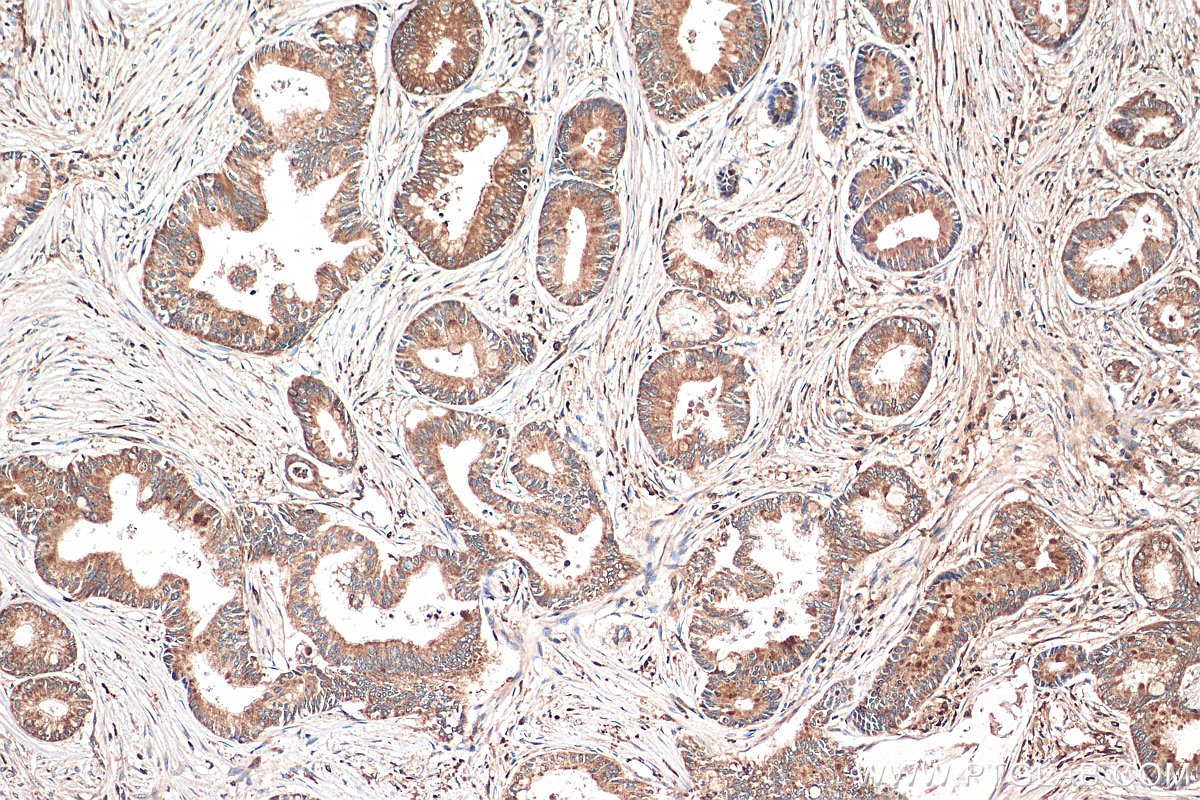

| Positive IHC detected in | human pancreas cancer tissue Note: suggested antigen retrieval with TE buffer pH 9.0; (*) Alternatively, antigen retrieval may be performed with citrate buffer pH 6.0 |

| Immunohistochemistry (IHC) | IHC : 1:50-1:500 |